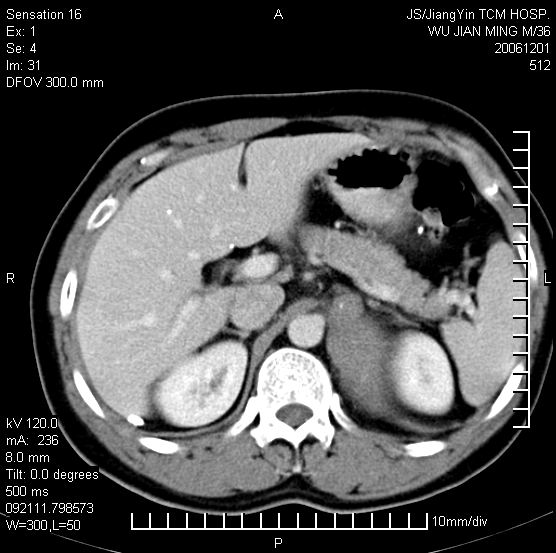

以下是引用dyqct在2006-12-1 21:17:00的发言:[br]左心缘旁及后肋膈窦区见巨大椭圆形混杂密度肿块,周围见大小不等斑片状钙化,内部无强化,周围包膜轻度强化,心脏明显受压变形,即明显占位效应,肿块广基与心包、膈相连。肝、脾内、肝门见多数小结节状钙化影。[br]考虑:1、左心缘旁及后肋膈窦区慢性包裹性胸膜炎(结核性);[br] 2、肝、脾及肝门淋巴结核已钙化。[br]

以下是引用zrs在2006-12-2 17:28:00的发言:[br]肺内、肝脾内虽有钙化,但不支持结核性胸胸膜炎包裹,而支持寄生虫感染![br][br]

以下是引用zyx168在2006-12-2 10:10:00的发言:[br][br]肝脾肺内多发钙化灶